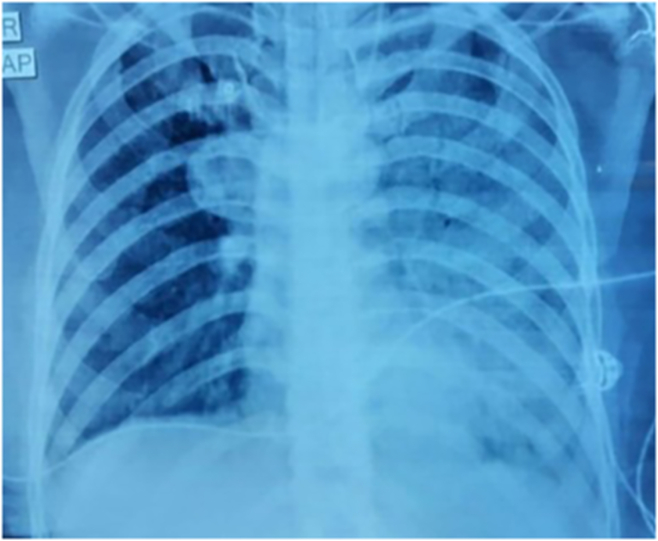

A 35-year-old female patient, non-smoker with no prior comorbidities presented with history of progressive breathlessness (Modified Medical Research Council (mMRC) grade I to mMRC Grade IV) and dry cough of 18 months duration. There was no history of any trigger factors, seasonal variation, haemoptysis, fever, wheeze or chest pain. There were no features of connective tissue disorders or vasculitis. She also gave history of frequent hospital admissions in the past 18 months and had become oxygen-dependant in the past 03 months. On arrival, patient was tachypnoeic (respiratory rate-28/min) and was having tachycardia (104/min). Her saturation at room air was 72% which improved to 94% with supplemental oxygen via nasal prongs at a flow of 6 L/min. Chest auscultation revealed bilateral basal inspiratory crackles. Other systemic examination was unremarkable. Her laboratory parameters showed leucocytosis (white blood cell count of 11,800/μL, neutrophil-59%, lymphoyte-32%), haemoglobin of 13.7 gm/dL and normal platelet count (2.17 lakh/μL). The metabolic and biochemical parameters were within normal limits. Arterial blood gas analysis showed PaO2-48 mmHg, PaCO2-32.9 mmHg and AaDo2 of 60 on room air and her ECG showed sinus tachycardia. Her 2-dimensional echocardiogram showed normal left ventricular ejection fraction (60%). The spirometry showed severe restrictive defect [forced vital capacity (FVC) - 1.17 L (47% of predicted) and forced expiratory volume (FEV) 1-0.88 L (41% predicted)]. The chest radiograph revealed bilateral alveolar infiltrates predominantly in the lower zone (Fig. 1A). High resolution computerised tomogram of chest showed diffuse ground glass haziness and interlobar septal thickening with crazy paving the appearance and dense consolidation of bilateral lower lobes (Fig. 1B). We also performed a videobronchoscopy on the patient which showed milky white lavage fluid and cytology showed dense granular amorphous proteinaceous material at places forming small globules which was periodic acid-Schiff (PAS) positive (Fig. 2A and B). She was suspected to be a case of PAP. To confirm the diagnosis, blood sample for anti-granulocyte-monocyte colony stimulating factor (anti GM-CSF) antibody was sent to Cincinnati Children's Hospital-United States, it showed raised titres of anti GM-CSF antibody [55.6 mcg/mL (normal<3.1 mcg/mL)] confirming the diagnosis of autoimmune PAP.

Fig. 1.

(A) Chest radiograph showing bilateral alveolar infiltrates in all zones. B) High resolution computed tomogram images showing dense bilateral consolidation with interlobar septal thickening with crazy paving appearance.